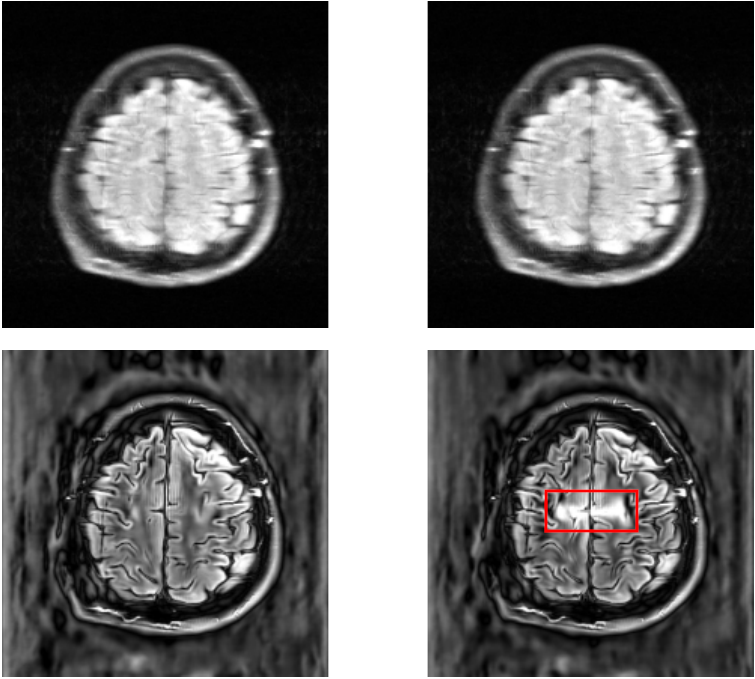

For a qualitative assessment of the results, we show some examples in figure˜0.B.1 for the UNet model and figure˜0.B.2 for the E2E-VarNet model of reconstructions where the attack was successful. These figures are structured as 2x2 panels of images where the first row displays the original and perturbed input samples and the second row displays the corresponding model-based reconstructions. Areas which we believe contain hallucinatory structures are highlighted in red.

We notice from LABEL:fig:unet-best1 and LABEL:fig:unet-best2 that the multi-coil images seem to be more vulnerable than the single-coil ones, in the sense that the resulting distortions are more severe for multi-coil data. The generated perturbations also seem easier to spot for single-coil data. This may be explained by the fact that perturbations in the multi-coil images can be more “spread out” across the coils, whereas with single-coil data this is not possible. This is consistent with the observation that vulnerability to adversarial examples increases with data dimensionality [14, 27]. Although we cannot compare to single-coil data for the E2E-VarNet, we do notice large distortions in LABEL:fig:varnet-best1 as well that go far beyond the boundaries of our inserted detail. On the multi-coil brain data, the hallucinations seem less severe for both models compared to the knee data, but the distortions can still be significant as they tend to resemble non-existent sulci. For knee images, the distortions appear to substantially change the structure of the knee joint, especially on multi-coil data.